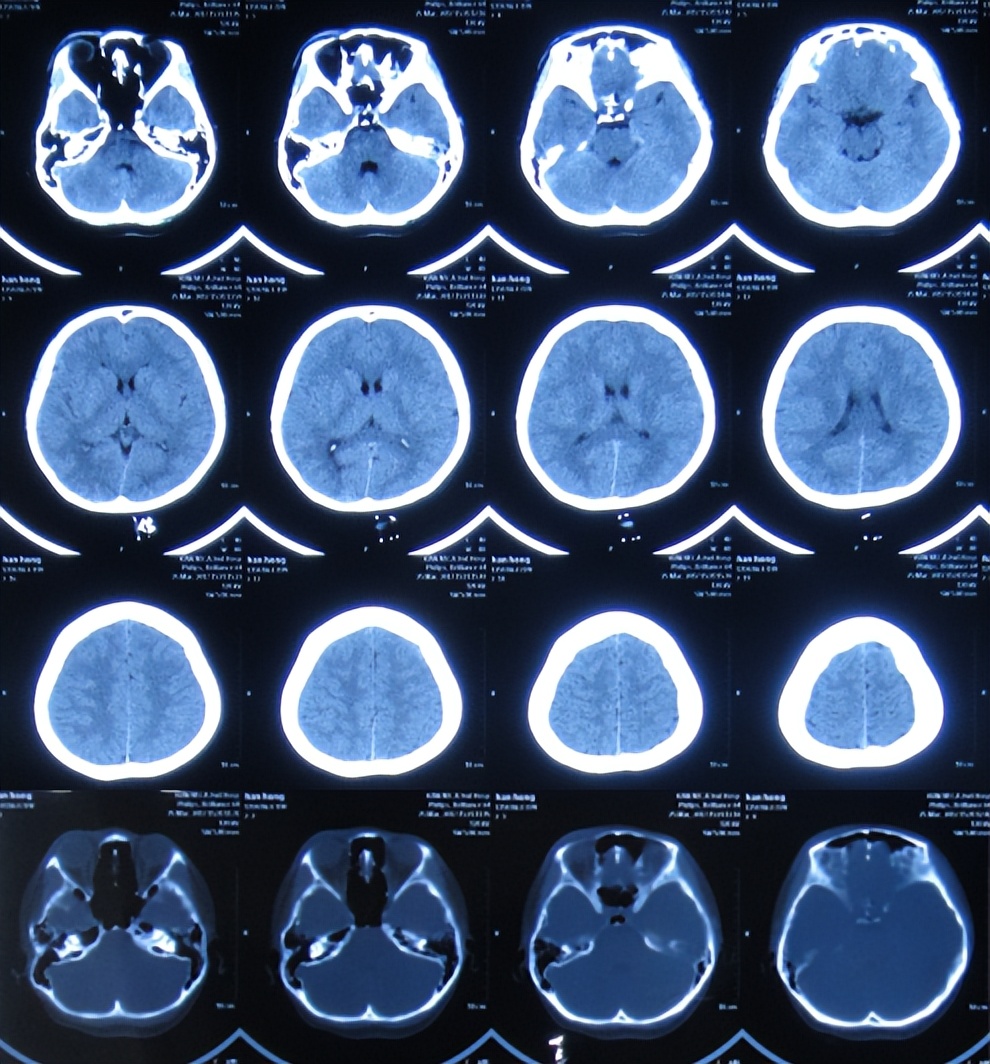

但发病后5天即2017年3月25日,从学校宿舍的上铺下来时因发热虚弱摔下,右眼眶外伤,就诊于第1家的陕西省西安某三甲医院,查脑CT( 图-1 )后认为右额颞部硬膜下有血肿,胸部X线检查未见异常(片子丢失)。

图-1: 2017年3月25日脑CT